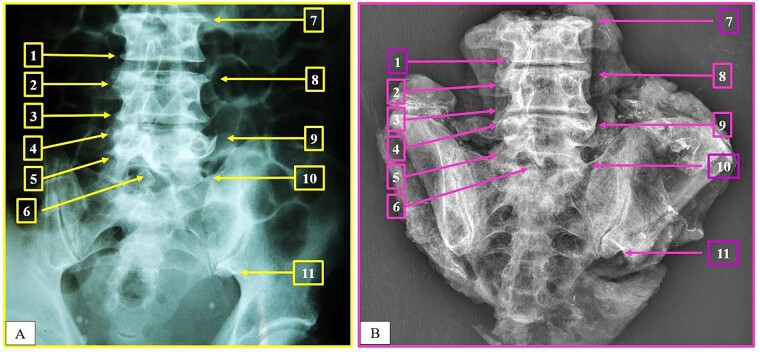

This article presents a series of three complex forensic cases that posed significant challenges for identifying human remains. These include a mass dam disaster, burnt human remains, and extensively decomposed human remains. Positive identification was achieved using a shadow positioning technique with imaging comparisons of medical findings. After establishing the biological profile, medical data were evaluated with digital radiography and computed tomography examinations the human remains. These aimed to replicate the original (intravitam) traits in the same angulation to examine postsurgical characteristics, as well as the anatomical, pathological, and morphological features, which were sufficient to establish a positive scientific identification. Technological advancements tend to reveal additional skeletal details, making medical data comparisons significantly more effective in the context of anthropological identification. These cases demonstrate that the possibility of identification should never be ignored, even in situations with advanced decomposition.

Key points: Conventional identification methods may not always be applicable in forensic anthropology cases.The presented cases include a mass dam disaster, burnt human remains, and extensively decomposed human remains.These three cases involved successful human identification with medical findings comparisons using the shadow position technique.Identification could be established in these cases, despite challenges, such as fire damage, an incomplete body, and extensive decomposition.These cases suggest medical findings should be considered as biological identifiers rather than secondary identifiers.